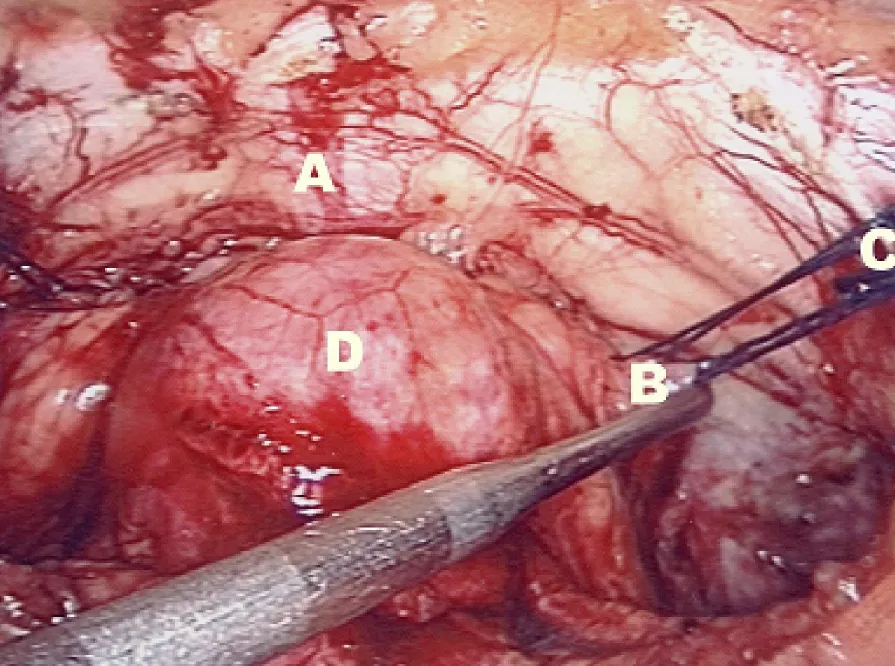

這題考的是腹腔鏡 Burch colposuspension 手術中,辨識 Cooper's ligament 的位置。圖片中,Cooper's ligament 是用來固定縫線以懸吊陰道旁筋膜的堅韌結構。